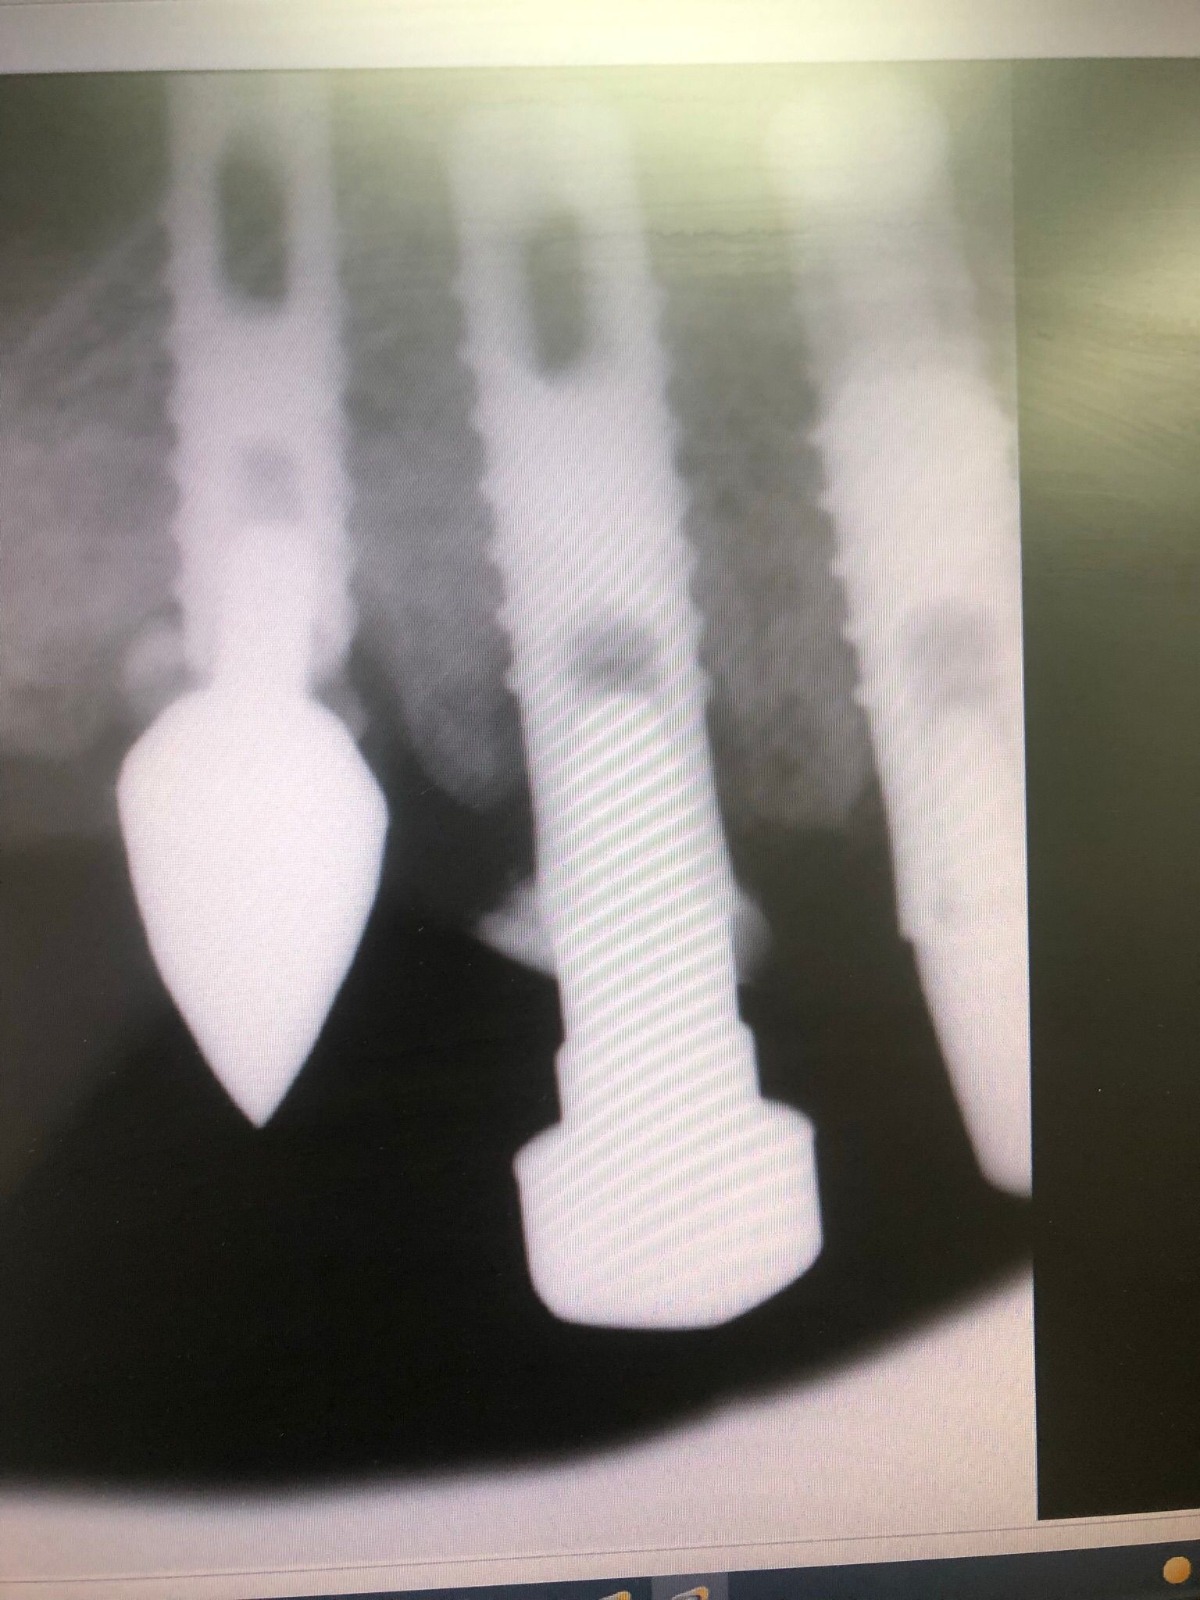

Actualmente vuelve el paciente de nuevo con la misma prótesis. Había roto dos de los tres pilares en concreto los más distales. El primero de los dos había roto la rosca del aditamento dentro del implante como ocurre habitualmente. Pero el ultimo pilar había roto directamente la cabeza del implante tal como se ve en la radiografía y lo que quedaba era un cilindro de titanio macizo perfectamente integrado en el maxilar, sin posibilidad de enroscar nada. Le explicamos al paciente que habría que quitar y poner un implante en el mismo acto. El paciente dijo que no, así que decimos que no se haría cirugía. Buscamos solución alternativa: hacemos un un agujero en el centro del macizo cilíndrico del implante roto y pasamos sucesivamente el set de machos roscantes. Utilizamos una fresa cañón de 1 mm que poco a poco se va introduciendo hasta 8mm con un poco de vagación, que hace que sea un poco mas de 1mm de diámetro. Posteriormente pasamos el conjunto de machos roscantes de métrica 2mm para poder usar un aditamento experimental, que era un palo de rosca de diámetro 2 mm unido a un cuerpo metálico en forma de sombrero napoleónico fabricado en cromo/cobalto, prototipos primitivos de la sistemática ASATIM y que tienen la característica de tener gran resistencia a la fractura. Nos llevó un tiempo largo el tallado de dichos aditamentos, tal como se puede observar en las imágenes, y tras cicatrizar la encía se le hizo una prótesis estándar. Esperemos que no lo rompa más veces.